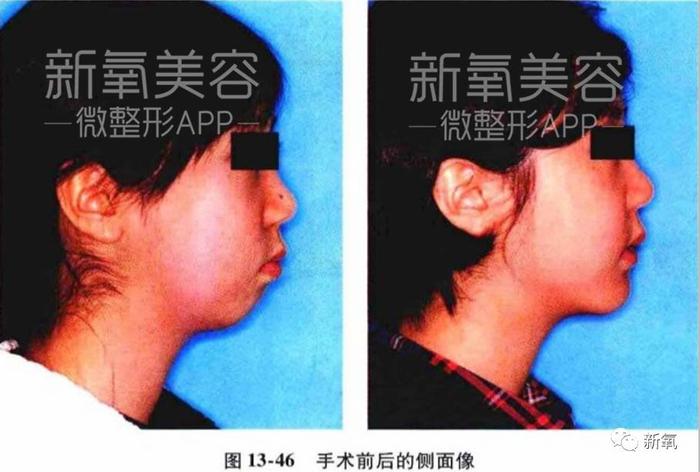

看下面这个真人案例,仅在整牙的矫正下,不仅下牙列回到正常的位置,连原本被限制发育、显得凹陷的中面部也变得正常,明显侧脸变得饱满了。

如果错过这个时期,骨骼全部定型后想要矫正这个问题,就只能动骨了···

而且仅将下颌骨推进去也无法让上颌再长出来,也就意味着:之后还需要将受到影响发育不足的鼻基底、鼻子补起来。(注意看右边的鼻基底和上颌依然是扁平的)